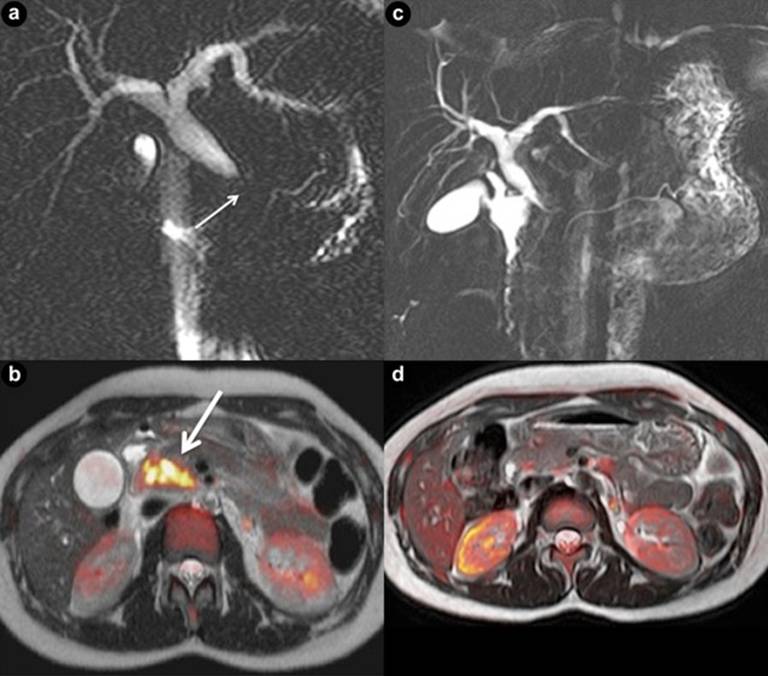

Patient #3

A 15-year-old girl originating from Burundi and living in Belgium since the age of 5, consulted for intermittent heart burn, epigastric pain and weight loss. Abdominal ultrasound and MRI revealed a pancreatic mass associated with common bile duct obstruction and lack of main pancreatic duct dilatation (Figure 3ab). EUS confirmed a heterogeneous, poorly vascularized mass within the pancreatic head, compressing the CBD. FNA showed granulomas with necrotic areas suggesting tuberculosis. Cultures for M. Tuberculosis were positive. She was treated successfully with anti-tuberculin therapy. The control MRI three months later showed a complete resolution of the pancreatic mass (Figure 3cd).

|

Figure 3. a. MRCP shows distal common bile duct obstruction (short arrow). Main pancreatic duct is not dilated. b. Coloured map of T2-weighted and Diffusion-weighted sections through the head of the pancreas displaying a space-occupying lesion with cellular proliferation (long arrow). Control MRI shows almost complete resolution of bile duct obstruction (c.) and a normal pancreatic head (d.). (Patient #3). |